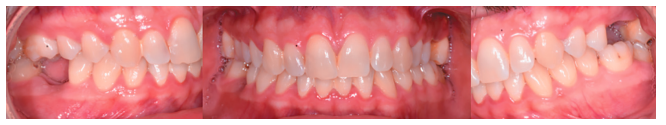

Caso clínico: se presenta el caso de un varón de 28 años, que acudió a consulta por la presencia de unos restos radiculares en localización de primer molar superior izquierdo. Se realizó un autotrasplante dental, siendo el diente donante el tercer molar superior izquierdo, que se trasplantó al alveolo del primer molar, mostrando buena evolución clínica y radiográfi ca.

Clinical case: a clinical case of a 28-yearold man is presented, who went to dental clinic for removal of left fi rst molar roots. An autotransplant was performed using left third molar as donor tooth, which was transplanted into fi rst molar alveolus, showing promising clinical and radiographic evolution.